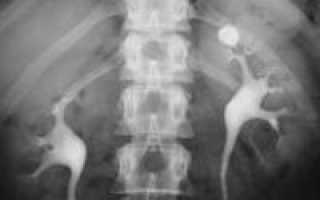

Ведущим методом выявления камней в почках служит рентгеновская диагностика. Большая часть конкрементов определяется уже при обзорной урографии. Однако белковые и мочекислые (уратные) камни почек не задерживают лучи и не дают теней на обзорных урограммах. Они подлежат выявлению с помощью экскреторной урографии и пиелографии. Кроме того, экскреторная урография дает информацию о морфо-функциональных изменениях в почках и мочевых путях, локализации конкрементов (лоханка, чашечка, мочеточник), форме и размерах камней в почках. При необходимости урологическое обследование дополняется радиоизотопной нефросцинтиграфией, МРТ или КТ почек.